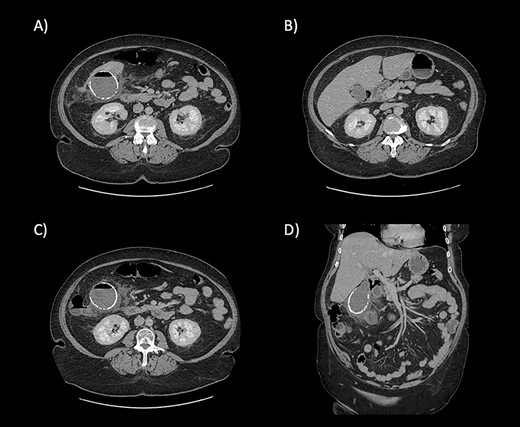

Blood tests on admission showed raised inflammatory markers (white cell count 11.3 × 109 /L; C-reactive protein 78 mg/L) and raised bilirubin 37 µmol/L. Alanine aminotransferase, alkaline phosphatase and renal function were all within normal limits. A contrast-enhanced computer tomography (CT) scan of the abdomen and pelvis demonstrated a calcified porcelain gallbladder and with features of emphysematous cholecystitis (Fig. 1).

CT scan images demonstrating the calcified wall of the gallbladder consistent with a porcelain gallbladder (A). Pericholecystic fluid and stranding (A and B) demonstrate cholecystitis. The presence of air within the wall and lumen of gallbladder is consistent with emphysematous cholecystitis (C). Air is also seen tracking along the hepatic hilum (D).